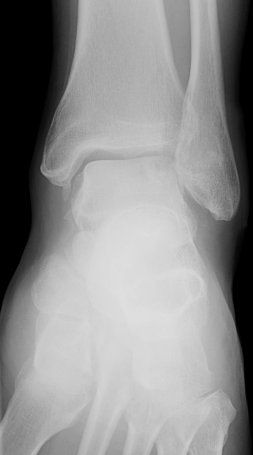

Return to Osteochondritis Dissecans